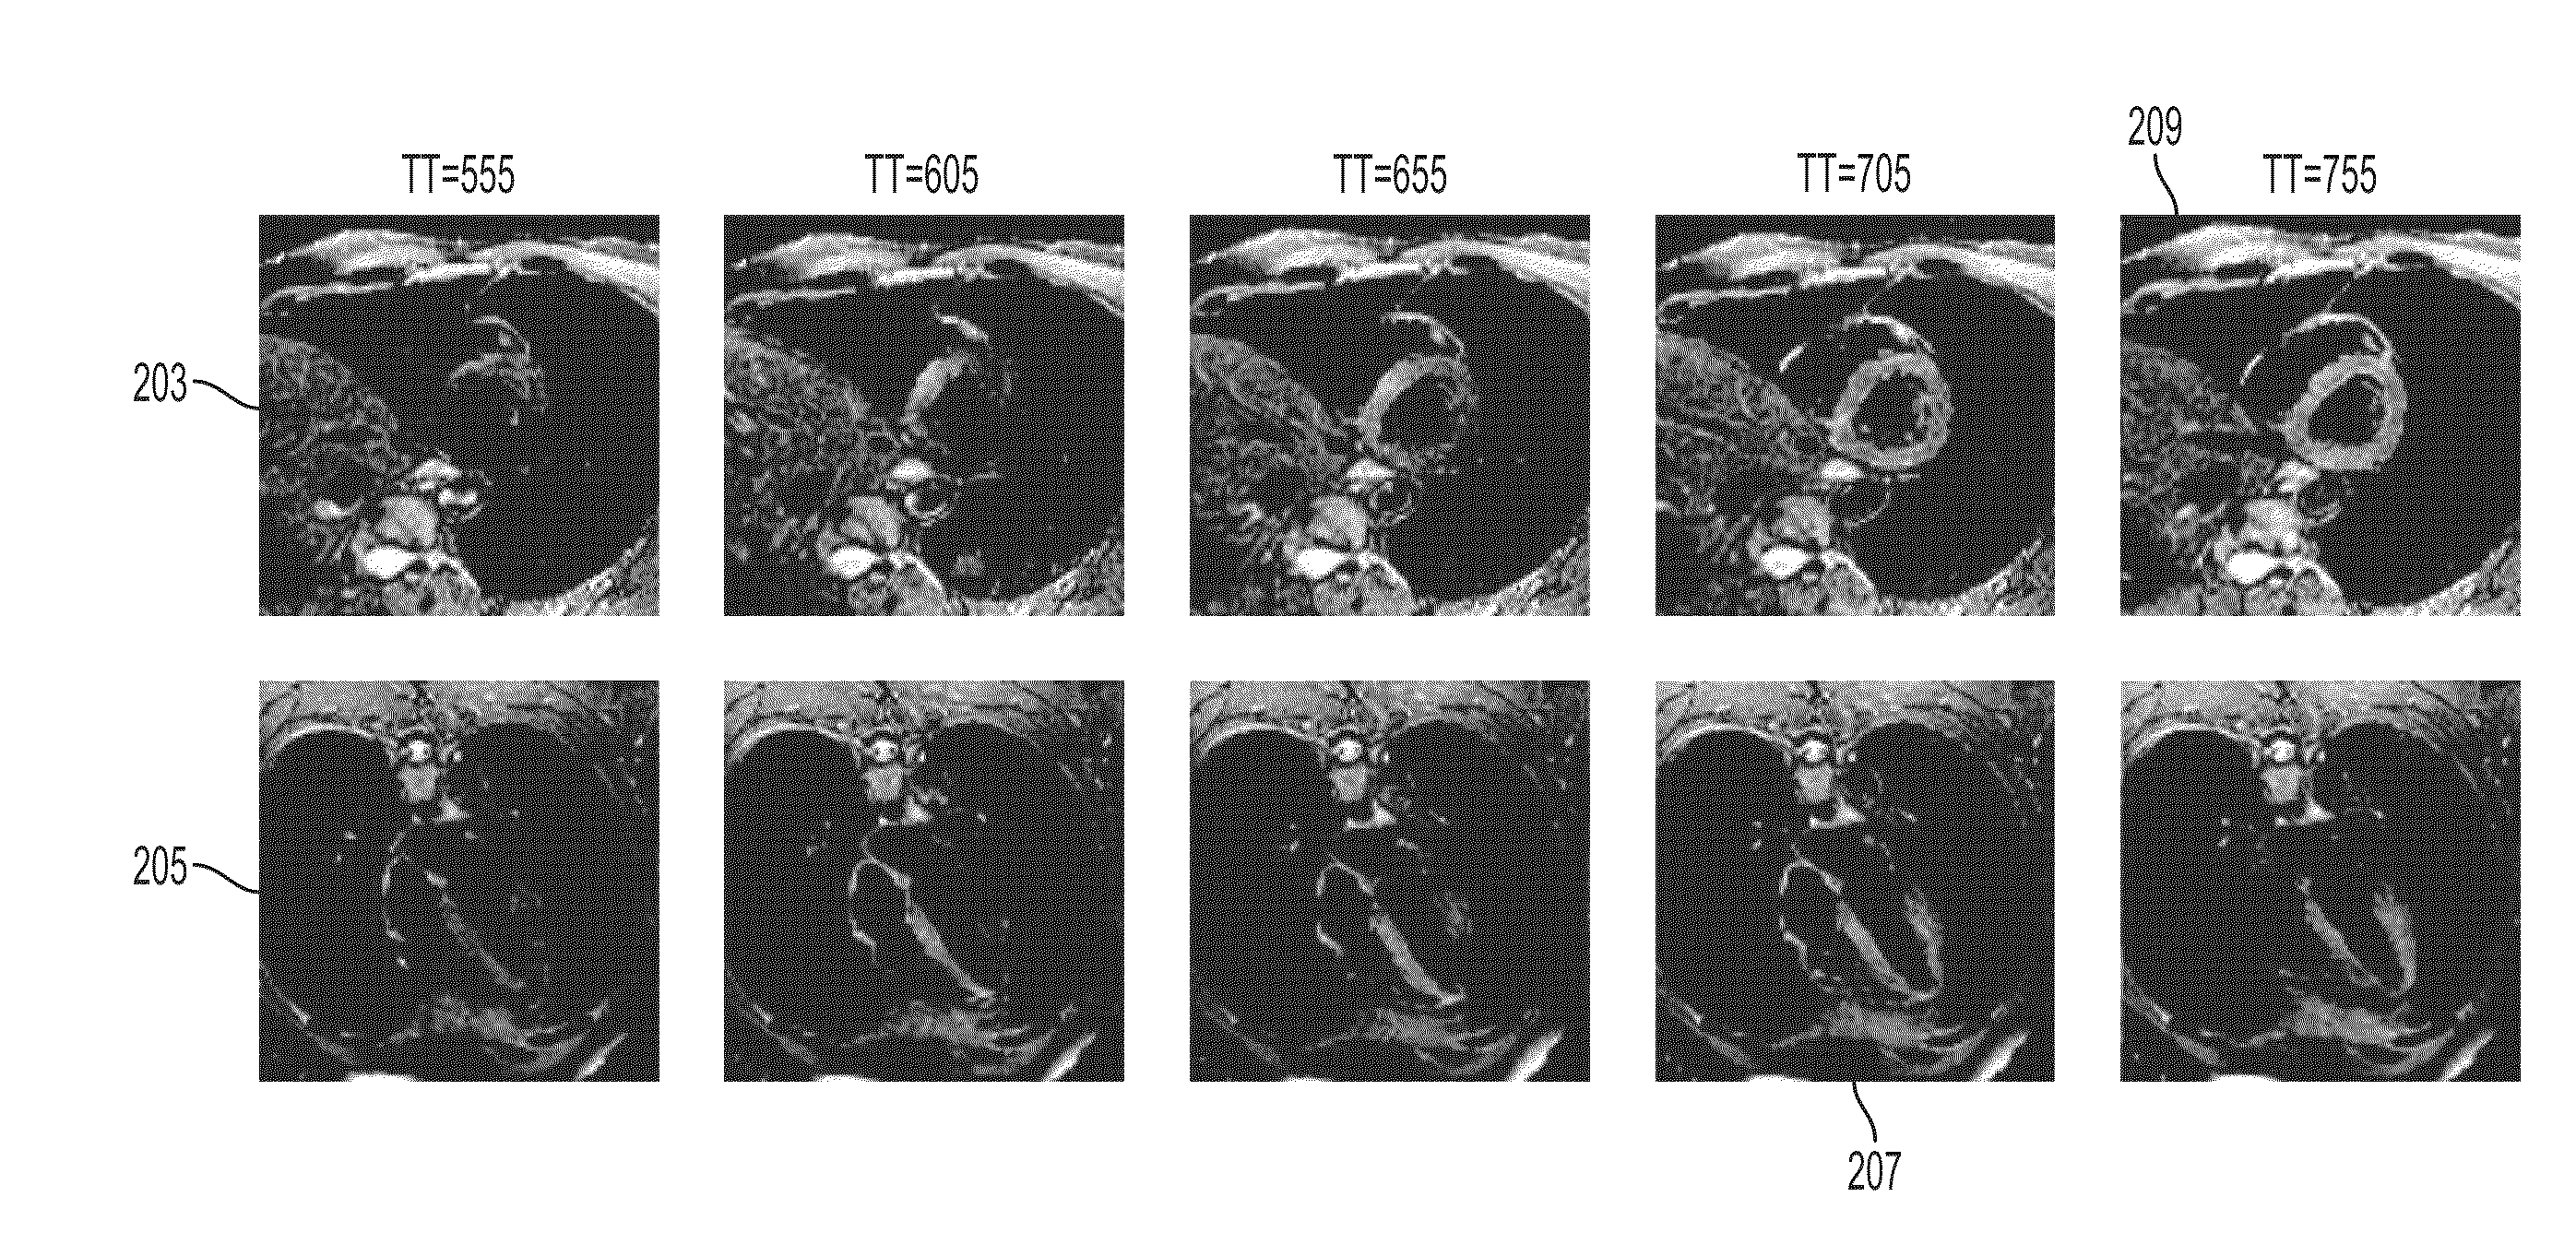

Automatic System for Timing In Imaging